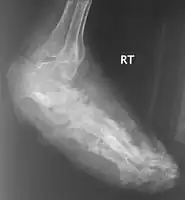

X rays and ultrasonography may be carried out to assess the extent of the disease. X rays findings are extremely variable. The disease is most often observed at an advanced stage that exhibits extensive destruction of all bones of the foot. Rarely, a single lesion may be seen in the tibia where the picture is identical with chronic osteomyelitis. Cytology of fine needle aspirate or pus from the lesion, and tissue biopsy may be undertaken sometimes.[9] Some publications have claimed a "dot in a circle sign" as a characteristic MRI feature for this condition (this feature has also been described on ultrasound).[12]

X-ray foot: mycetoma